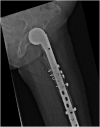

We report an 85-year-old patient with severe osteoporosis who had suffered from multiple episodes of periprosthetic fracture of the femur. Revision fixation with long-spanning cable plate for bisphosphonate-induced atypical periprosthetic femoral fracture was performed. Nonunion and implant failure occurred at 16 months requiring revision surgery using long-stem femoral prosthesis with cable-plate fixation. To further facilitate bone healing, allograft and bone morphogenetic protein (BMP) were added. Eventually bone union was achieved after one year.